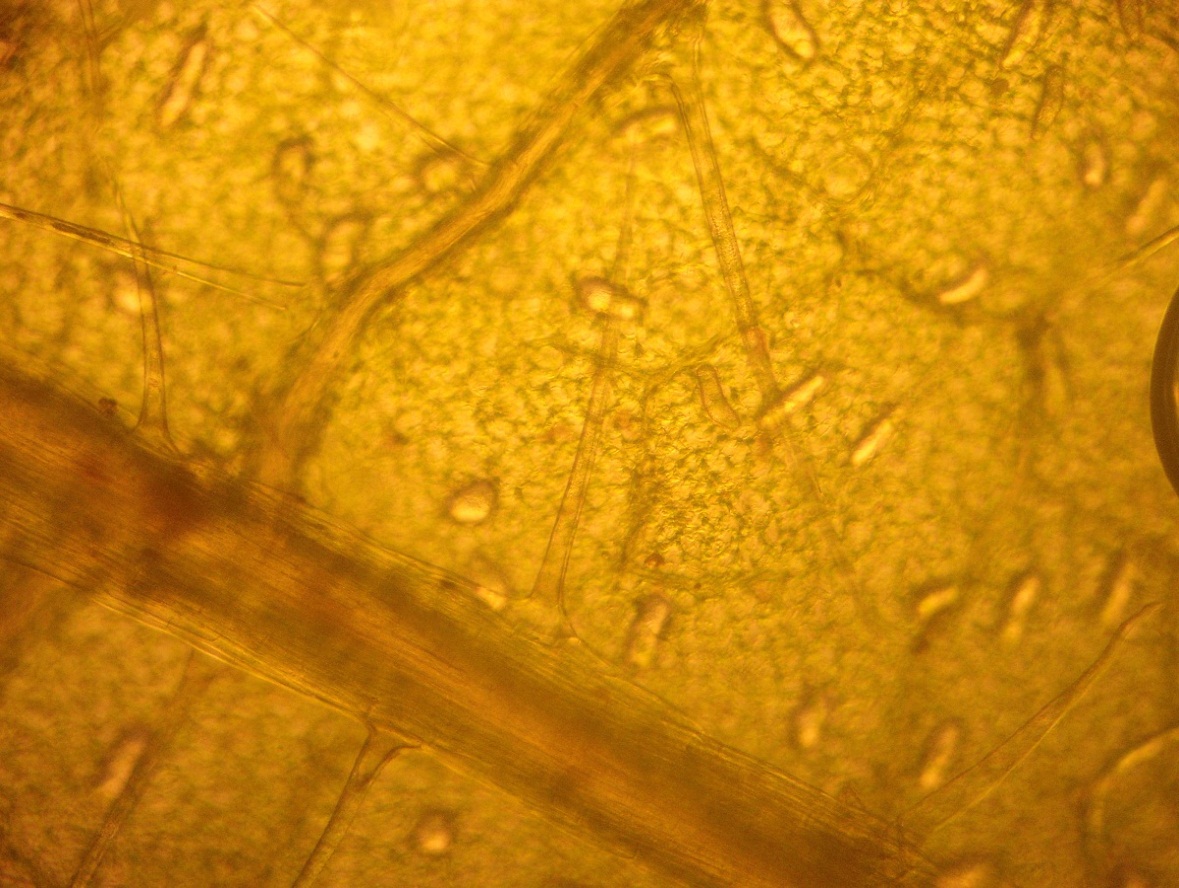

Важным диагностическим признаком являются рассеянные по всей поверхности листа многочисленные сосочковидные и конусовидные волоски с бородавчатой поверхностью (рис.13). На нижней стороне листа в небольших углублениях расположены эфирномасличные железки, состоящие из 8 радиально расположенных клеток и одноклеточной короткой ножки. [1]

Рис.13. Многоклеточные волоски листа мелиссы

- На основе проведенного микроскопического анализа были обнаружены диагностические признаки Мяты перечной (извилистые клетки эпидермиса, эфирномасличные вместилища) и Мелиссы лекарственной (клетки эпидермиса c извилистыми стенками, устьица аномоцитного типа, железистые волоски).